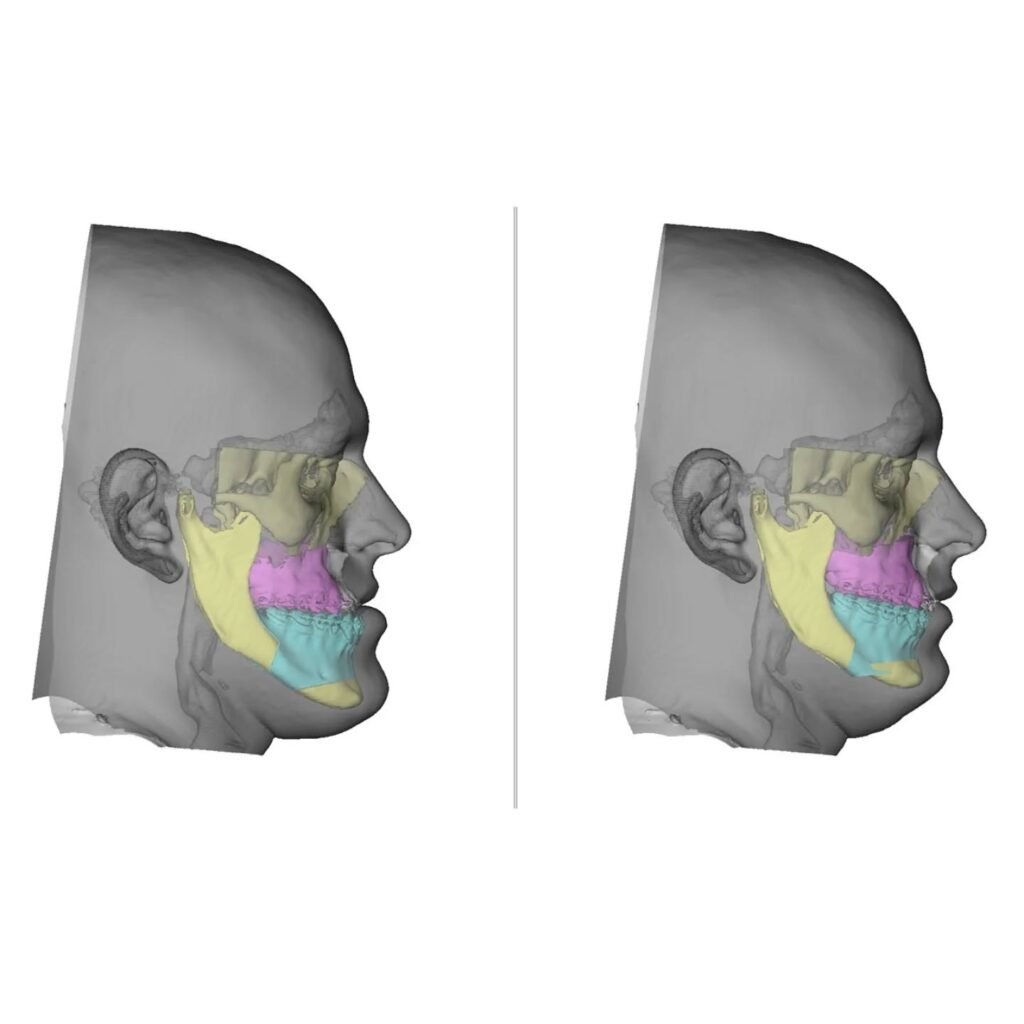

Cirurgia Ortognática

Você sente dificuldade para morder, falar ou até mesmo respirar corretamente? A Cirurgia Ortognática pode ser a solução! Esse procedimento corrige alterações ósseas no maxilar e mandíbula, melhorando a função mastigatória, a harmonia facial e a qualidade de vida.

Dr. Guilherme Rosetti é Cirurgião Bucomaxilofacial e Especialista em Harmonização Orofacial, com sólida formação nacional e internacional. É graduado em Odontologia pela Universidade Federal do Paraná (UFPR) e especialista em Cirurgia e Traumatologia Buco-Maxilo-Facial pela PUC-RS. Possui pós-graduações em Cirurgia Oral Menor (ABO-PR), Artroscopia da ATM (IECS) e Cirurgia Ortognática Minimamente Invasiva (ITC), além de fellowship em Cirurgia da ATM pela JRG Odontologia. É também especialista em Harmonização Orofacial com registro oficial pelo CFO, com formação em Toxina Botulínica e Preenchimento Orofacial pelo Instituto Ziroldo. Conta com diversas habilitações técnicas, incluindo Ozonioterapia, Laserterapia, Sedação Consciente e Venopunção com I-PRF. Completou treinamentos de alto nível como o Virtual Planning in Orthognathic Surgery pela KLS Martin (Alemanha), o L1 MI Orthognathics – ITC Brasil e o curso da SORG Academy em Viena (Áustria), voltado à Cirurgia da ATM. É membro do Colégio Brasileiro de CTBMF e da Latin American Society of TMJ Surgeons (LASTMJS). Com mais de 20 anos de experiência, atua nos principais hospitais de Curitiba, sendo referência nacional em cirurgia ortognática, cirurgia da ATM, implantes, reconstruções ósseas e harmonização facial avançada, com foco em precisão técnica, estética e recuperação funcional de excelência.

Etapa I: avaliação (ortodontista + cirurgião)

Etapa II: preparação (ortodontia)

Etapa III: cirurgia

Etapa IV: acompanhamento pós-operatório

Etapa V: acompanhamento